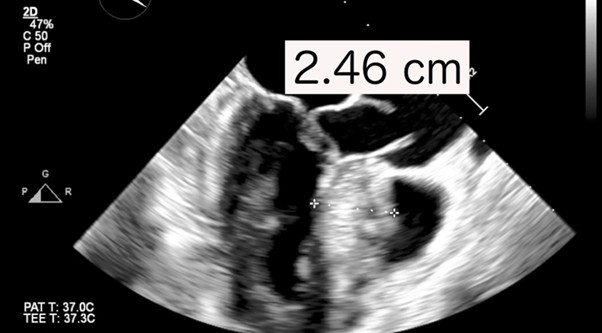

The authors present a symptomatic 54-year-old woman with hypertrophic obstructive cardiomyopathy (HOCM) and severe mitral regurgitation (MR). A transesophageal echocardiogram (TTE) showed asymmetrical interventricular septal hypertrophy measuring 2.46 cm with severe mitral regurgitation due to intrinsic mitral disease (annulus dilatation and posterior leaflet prolapse) and systolic anterior motion (SAM), which contributed to the obstruction of the left ventricular outflow tract (LVOT) with mean and max gradients of 55 mmHg and 123 mmHg, respectively (Figure 1).

Figure 1. (a) Preoperative transesophageal echocardiogram shows a bulging septum (a, between the two white +Trans.) [b] Left ventricular outflow tract mean and peak gradients.